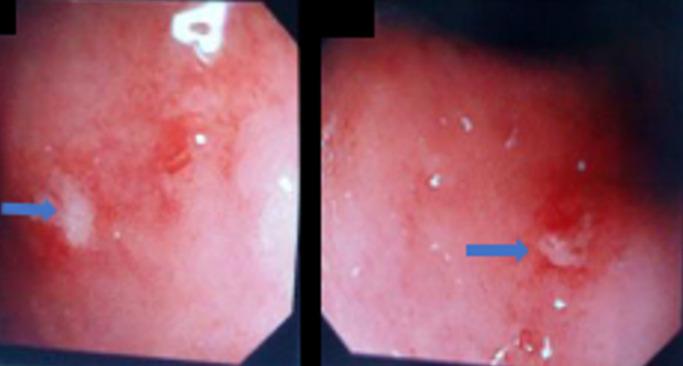

Since it was first documented in 1948 by Sir William Heneage Ogilvie, numerous cases of Ogilvie syndrome have been described in literature due to various medical and surgical causes. Nonetheless, only a handful of cases only have been documented due to underlying Acquired Immunodeficiency Syndrome (AIDS). A 41-year-old female was admitted with an acute abdomen secondary to partial mechanical intestinal obstruction or paralytic ileus based on signs and symptoms and Abdominal X-Ray (AXR). She was known to be HIV/AIDS WHO clinical stage II on treatment. On diagnostic imaging studies she had distended large bowels without features of mechanical intestinal obstruction and the diagnosis of Ogilvie syndrome was suspected after other differentials were excluded. Early recognition and appropriate management are essential, because if left untreated the bowel distension may progress to caecal perforation and fatal peritonitis. Medical imaging with Computer Tomography (CT) scan and colonoscopy has helped in achieving an accurate diagnosis and avoiding unnecessary laparotomies. Although an uncommon disorder, for earlier and accurate diagnosis a high index of suspicion is required by clinicians and radiologists who are treating patients with underlying HIV/AIDS. Ogilvie's syndrome is a rare condition and if missed can be fatal. In patients with HIV/AIDS, the symptoms may be directly due to HIV infection, secondary to opportunistic infections or possible neurotoxic effects of HIV treatment or lack of vitamin and minerals. It is important to exclude Ogilvie syndrome in patients from surgical causes of the acute abdomen to avoid unnecessary surgical procedures.

一名 41 岁女性因急性腹痛入院,病因是部分机械性肠梗阻或麻痹性肠梗阻,依据是症状和体征以及腹部 X 光(AXR)。她已知是接受治疗的艾滋病病毒/艾滋病世界卫生组织临床阶段 II 期患者。在诊断性影像学研究中,她的大肠膨胀,但没有机械性肠梗阻的特征,排除其他鉴别诊断后,怀疑为奥吉尔维综合征。早期识别和适当的治疗至关重要,因为如果不治疗,肠膨胀可能进展为盲肠穿孔和致命性腹膜炎。计算机断层扫描(CT)扫描和结肠镜检查的医学影像学有助于做出准确的诊断并避免不必要的剖腹手术。